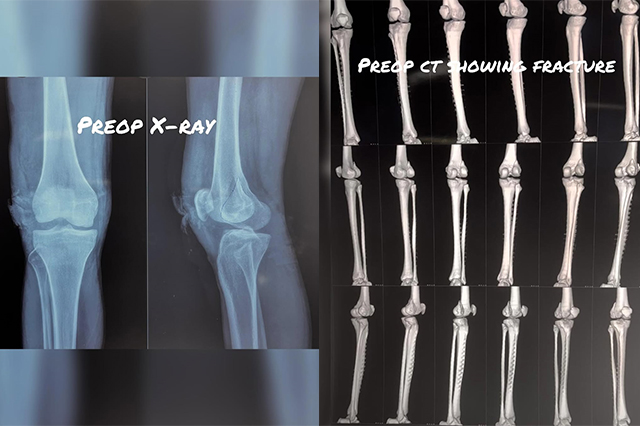

Hip-Knee-Replacement